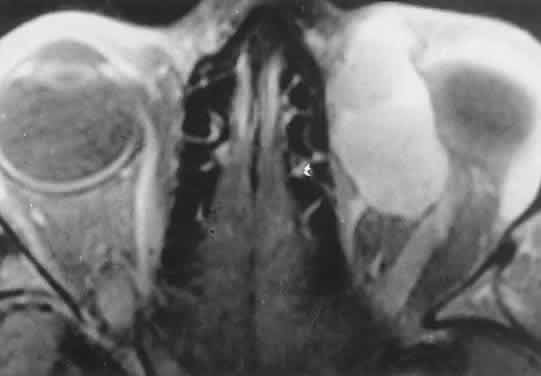

Fig. 2. MRI shows an intraconal tumor of lower intensity than the medial rectus

muscle. The proximal muscle is splayed rather than compressed, suggesting

that the lesion originated within the medial rectus. The diagnosis

was alveolar rhabdomyosarcoma. Fig. 2. MRI shows an intraconal tumor of lower intensity than the medial rectus

muscle. The proximal muscle is splayed rather than compressed, suggesting

that the lesion originated within the medial rectus. The diagnosis

was alveolar rhabdomyosarcoma.